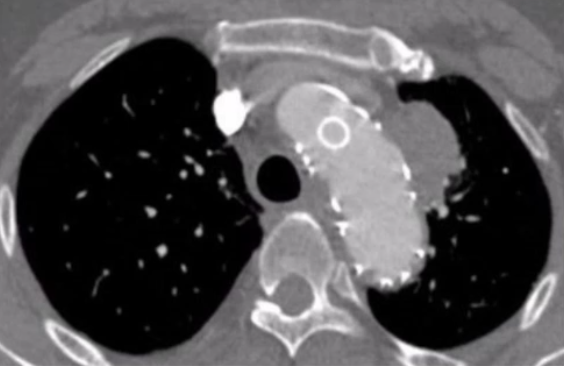

★ 左侧颈总动脉重建

从预先切开好的左侧颈总动脉穿刺送入6f动脉鞘,将鞘头顶在覆膜支架上,使用asahi treasure 12导丝顺利突破覆膜区。

先后导入4mm、6mm和8mm球囊对覆膜区进行扩张。考虑到患者颈总动脉存在较严重的动脉硬化,为避免置入大血管鞘带来的风险,选择使用10-40mm自膨式裸支架重建左颈总动脉,使用10-60mm球囊进行后扩张。扩张后,支架形态满意,成功恢复了左侧颈总动脉血流。

图1

图2

图3

更换MUSTANG 8-40mm球囊进一步扩张开窗处(图2)